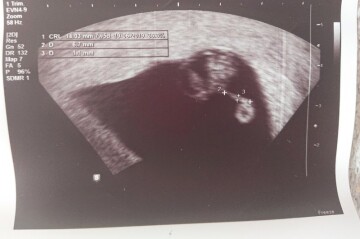

Dobry den, chtela bych se zeptat. Jsem dle posledniho utz 7tt+5, plod 14 mm, srdecni akce patrna, vse v poradku. Nicmene ve zprave od doktorky je veta: mezi embryem a zloutkovym vackem vs amnialni pruh 6.7mm sily 1.5 mm. Je tento stav pro zdravi a vyvoj ditete nebezpecny? Prikladam fotku z utz, dekuji

Dobrý den škoda že Vám situaci neozřejmila přímo vyšetřující lékařka takto "nadálku" to nemusí být srozumitelné ...amniální pruh je vazivový pruh vzniklý pravděpodobně po přechodném samovolném krvácení do dutiny děložní v prvních týdnech gravidity. Tento pruh či pruhy vedou napříč dutinou děložní či poze po jejím kraji a ve velmi výjimečných případech mohou omezovat pohyb některých částí plodu - prsty , končetiny. Velmi zřídka se mohou v souvislosti s těmito "pruhy" vyskytnou závažné vady končetin. Nicméně pokud lékařka napsala do zprávy vs, ´pak je to pouze podezření a nemusí se o amniální pruh jednat, Důležitý je určitě prvotrimestrální screening ve 12. týdnu, který by případné strukturální vady vyloučil